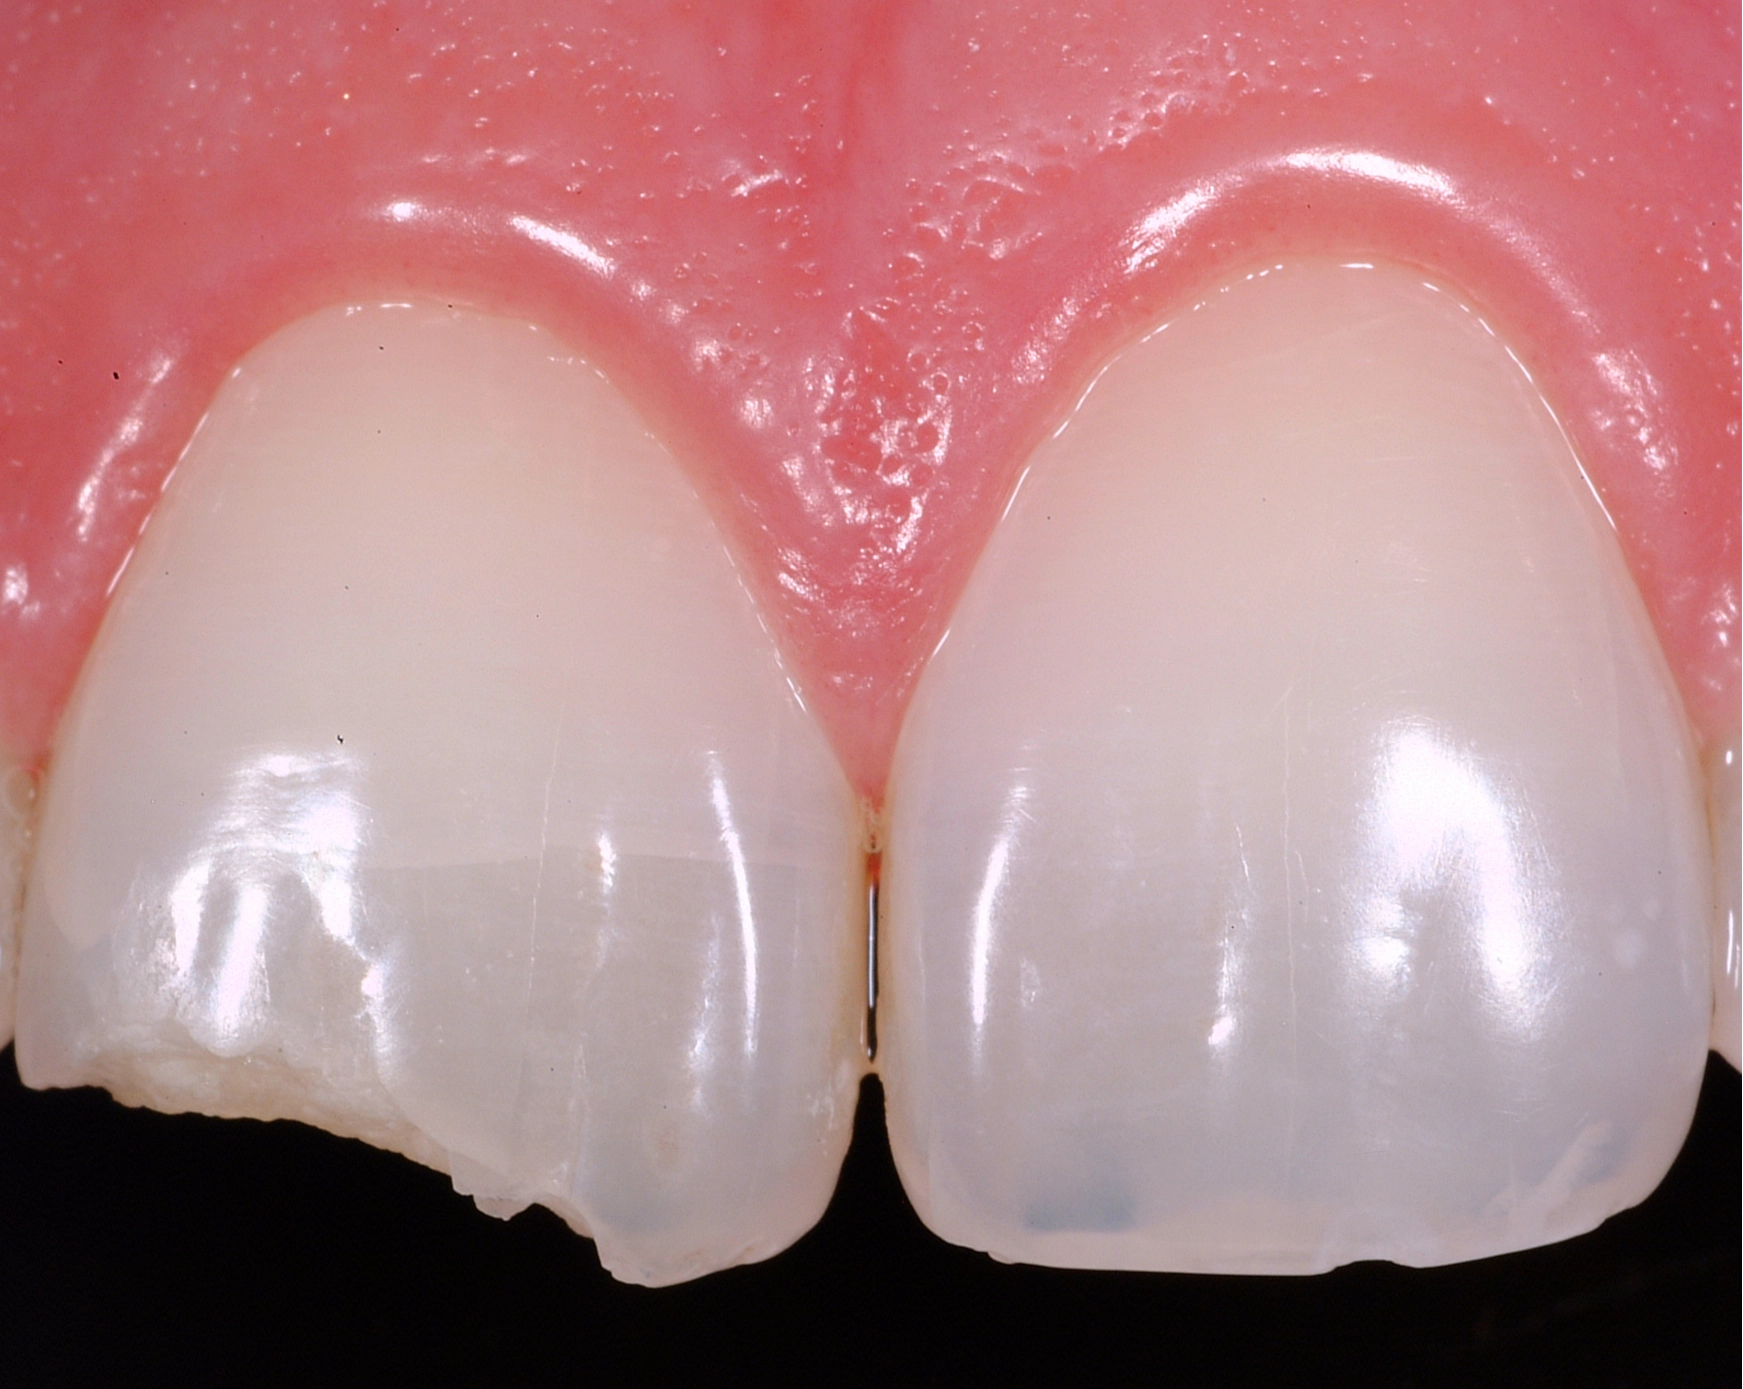

Courtesy of the Bioclear Learning Center

What Are Black Triangles?

Black triangles are small dark spaces that appear between teeth near the gums. They commonly develop due to:

- Gum recession

- Bone loss

- Tooth shape that narrows toward the gumline

- Orthodontic movement

These spaces can make teeth appear aged, trap food, and affect the balance of your smile.

Bioclear is one of the most predictable non-surgical ways to eliminate black triangles and restore a fuller, more youthful appearance.